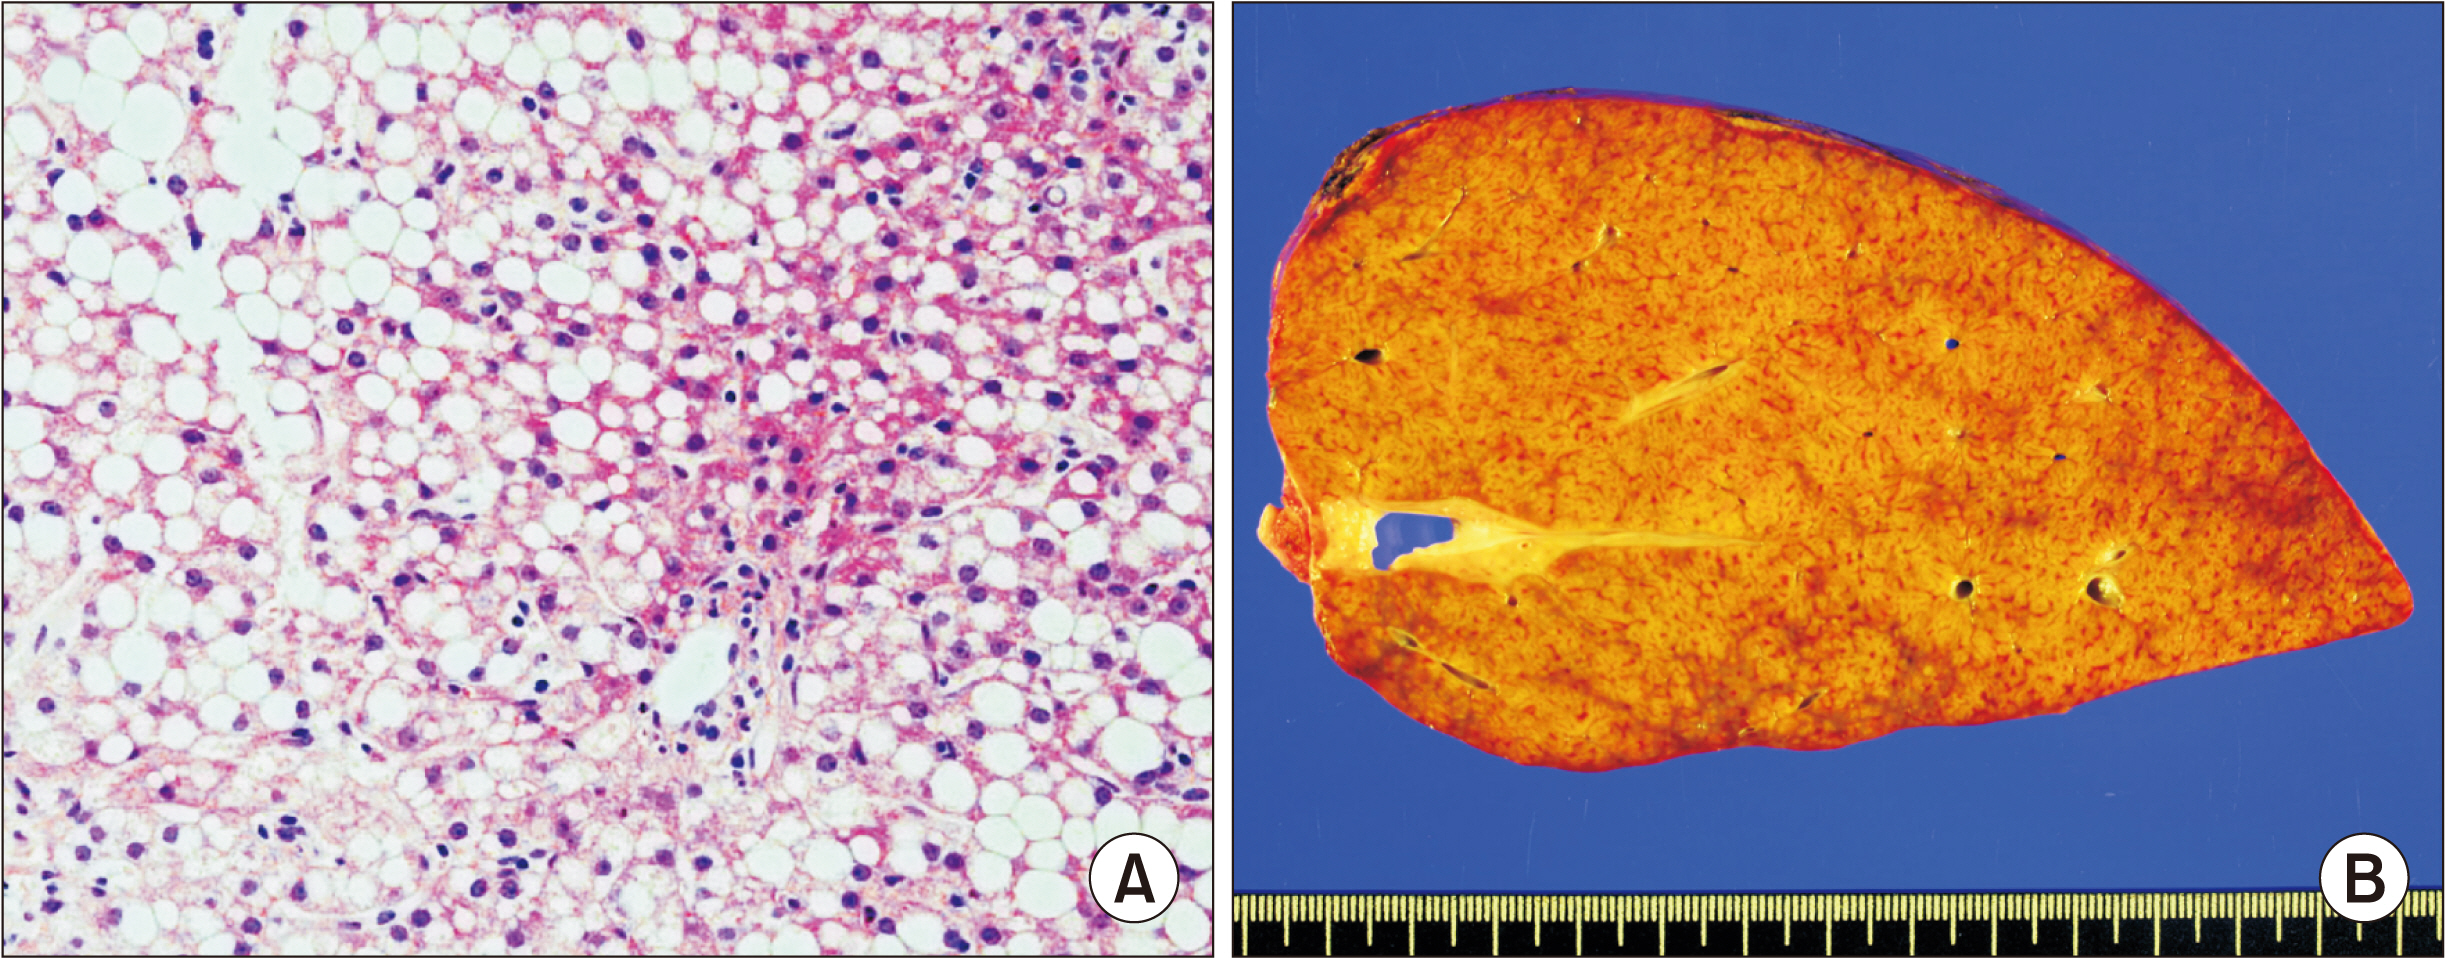

Two and five patients were diagnosed with PFIC type 1 and type 2, respectively. For all seven patients, age of PFIC onset was at birth. Jaundice was present in all cases. Mean pretransplant total and direct bilirubin levels were 16.1 ± 8.1 mg/dL and 12.4 ± 6.2 mg/dL, respectively. Median patient age and body weight at LT were 10 months and 7 kg, respectively. Types of donors were mothers of patients in four and deceased donors in three. All five patients with PFIC type 2 recovered uneventfully. One patient each with PFIC type 1 underwent retransplantation due to graft failure or died due to multi-organ failure. Overall graft and patient survival rates at five years were 66.7% and 83.3%, respectively. Bile salt export pump immunohistochemical staining showed normal canalicular expression in two patients with PFIC type 1, focal loss in two patients with PFIC type 2, and total loss in three patients with PFIC type 2.

LT is currently the only effective treatment for PFIC-associated end-stage liver diseases. It is mandatory to perform regular follow-up due to the risk of complications including steatohepatitis, especially for patients with PFIC type 1.